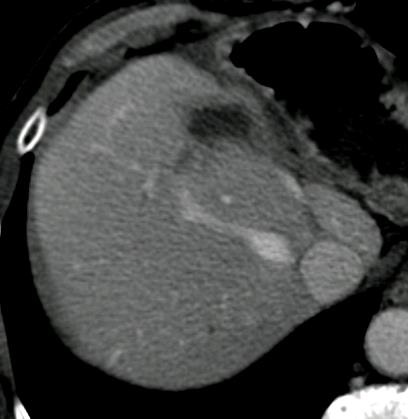

![]() ![]() ![]() ![]() 此图片的顺序待整理(查原文) ![]() ![]() ![]() ![]() Histologically-Proven Efficacy of Bland Embolization in a Patient with Net Liver Metastasis TAE 适应症之三:GIST